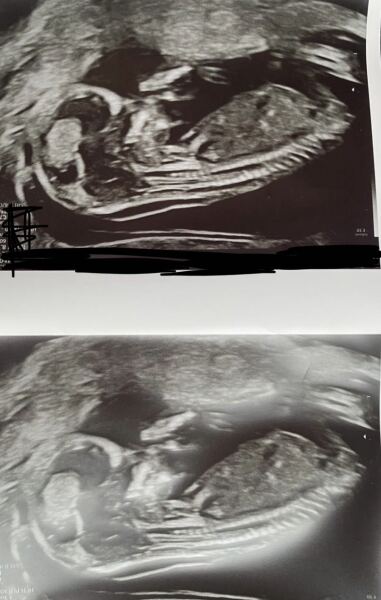

Boy or Girl?

what do you think?? Thanks